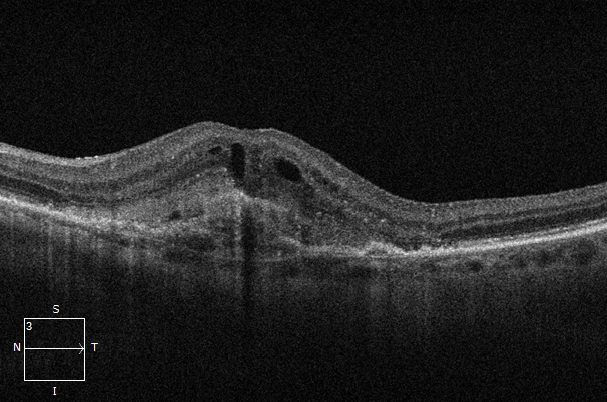

Entwicklung nach 2 Medikamenteneinspritzungen im Augenzentrum Gera am Elsterufer. Auf dem Netzhautfoto (Abb. 1) und dem Makula-OCT VOR der Behandlung (Abb. 2) ist ein typischer Befund der feuchten AMD zu sehen. Im Makula-OCT derselben Netzhaut (Abb. 3) ist NACH 2 Spritzen ein deutlicher Rückgang der Aktivität zu erkennen. Zum Vergleich zeigt Abb. 4 eine gesunde Netzhaut.